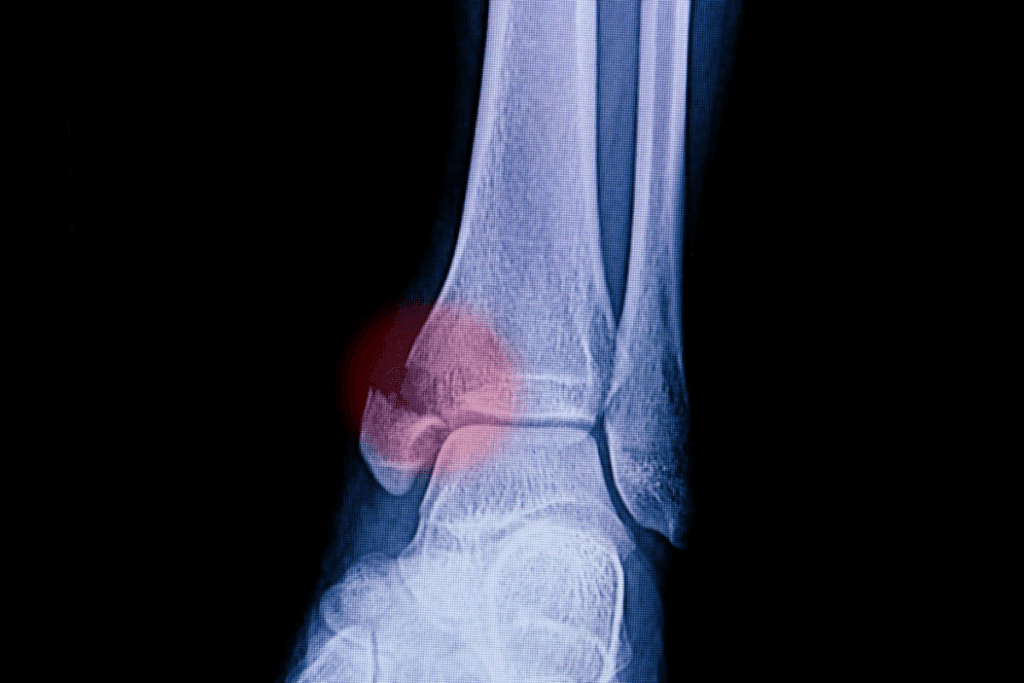

Advanced imaging guides our decisions. CT scans reveal hidden cracks, while X-rays confirm alignment after manual adjustments. Missed fractures risk improper healing, leading to chronic pain or arthritis.

X-rays remain our first-line tool, detecting 92% of bone displacements. For complex cases involving cartilage damage, CT scans map fracture lines in 0.5mm detail. When ligament evaluation becomes critical, MRI reveals soft tissue tears invisible to other methods.